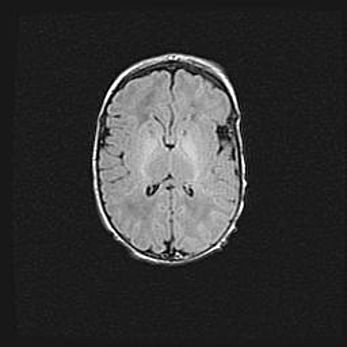

Ниже представлена  галерея МРТ снимков, полученных с применением LMT неонатальных матричных РЧ катушек. Также каждая группа МРТ снимков сопровождается информацией о пациенте (диагноз, возраст, вес, пол, срок гестации) и краткой сопроводительной расшифровкой диагноза.

Церебральная ишемия II.

Возраст: 5 дней

Вес: 3400 г

Пол: женский

Окружность головы: 35 см

Срок гестации: 39 недель

Церебральная ишемия – это заболевание, характеризующееся недостаточностью (гипоксией) либо полным прекращением (аноксией) снабжения мозга кислородом по причине закупорки одного или нескольких сосудов. Это приводит к  что метаболическим расстройствам различной степени тяжести в тканях головного мозга, развитию коагуляционных некрозов и гибели нейронов.